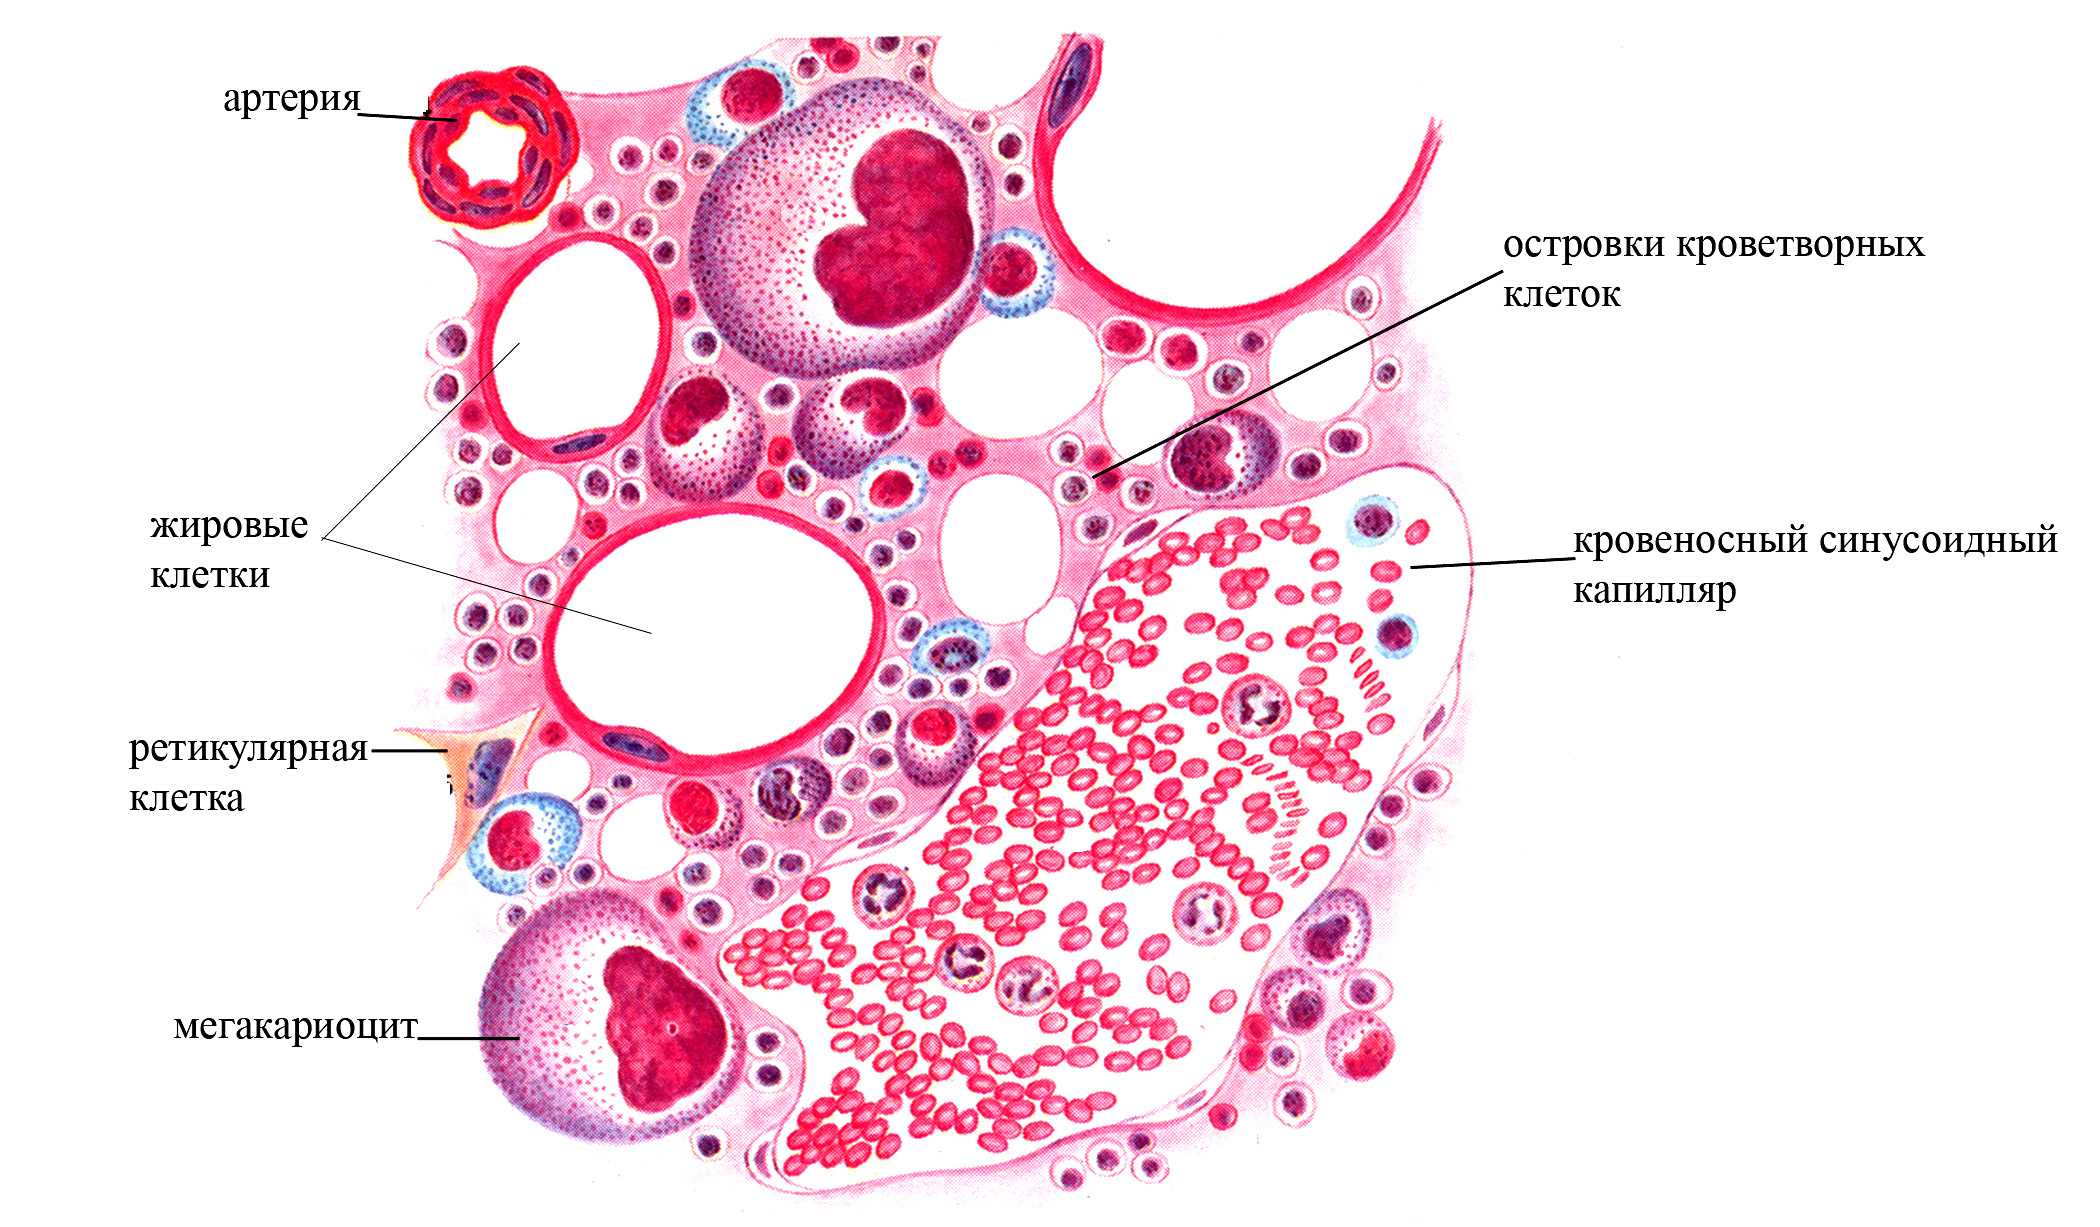

Изучение костного мозга: анатомия и функции